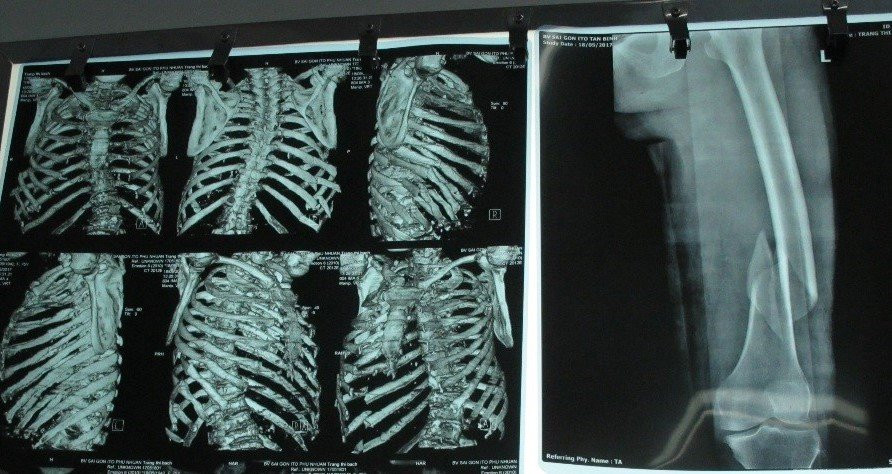

Bệnh nhân là cụ bà T.T.B (ngụ Bà Rịa), được chuyển từ bệnh viện tỉnh Bà Rịa lên trong tình trạng nguy kịch với các triệu chứng khó thở, tràn dịch màng phổi bên phải, gãy 8 xương sườn, gãy xương đùi phải và theo dõi tình trạng chấn thương gan.

8 xương sườn của bà B. bị gãy do bị bò đá.

Qua kiểm tra, xét nghiệm, các bác sĩ nhận định phải phẫu thuật khẩn cấp, nếu để muộn, bệnh nhân có thể tử vong vì mất máu và chèn ép đường thở. Ngay lập tức, bệnh nhân được đưa vào phòng mổ cấp cứu để dẫn lưu máu đọng trong phổi, cố định phần xương gãy.

Bác sĩ Nguyễn Thành Tâm, Giám đốc Bệnh viện cho biết: “Cụ bà thể trạng gầy yếu, tuổi cao mà chịu nhiều chấn thương nặng, mất máu nhiều nên ưu tiên các kỹ thuật cứu sống bệnh nhân trước. Nếu sau một tuần, sức khỏe bệnh nhân diễn tiến tốt, bệnh nhân sẽ được mổ xếp lại xương đùi. 8 xương sườn bị gãy, tạm thời chưa thể mổ vì cần theo dõi thêm”.